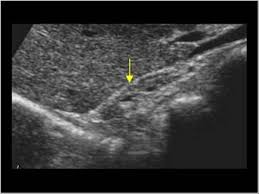

Kidney Ultrasound Adrenal Glands. It s hard to see normal adult adrenals on ultrasound despite being near the kidneys review of the adrenals in an adult is not part of the routine kidney ultrasound. An outer cortex and an inner medulla.

Details of the adrenal glands. High resolution real time sonography allows visualization of normal adrenal glands in 71 92 of adults. The normal ascent of the kidneys allows the organs to take their place in the abdomen below the adrenal glands. The left adrenal gland is imaged by a posterolateral approach in coronal plane through the long axis of the left kidney.